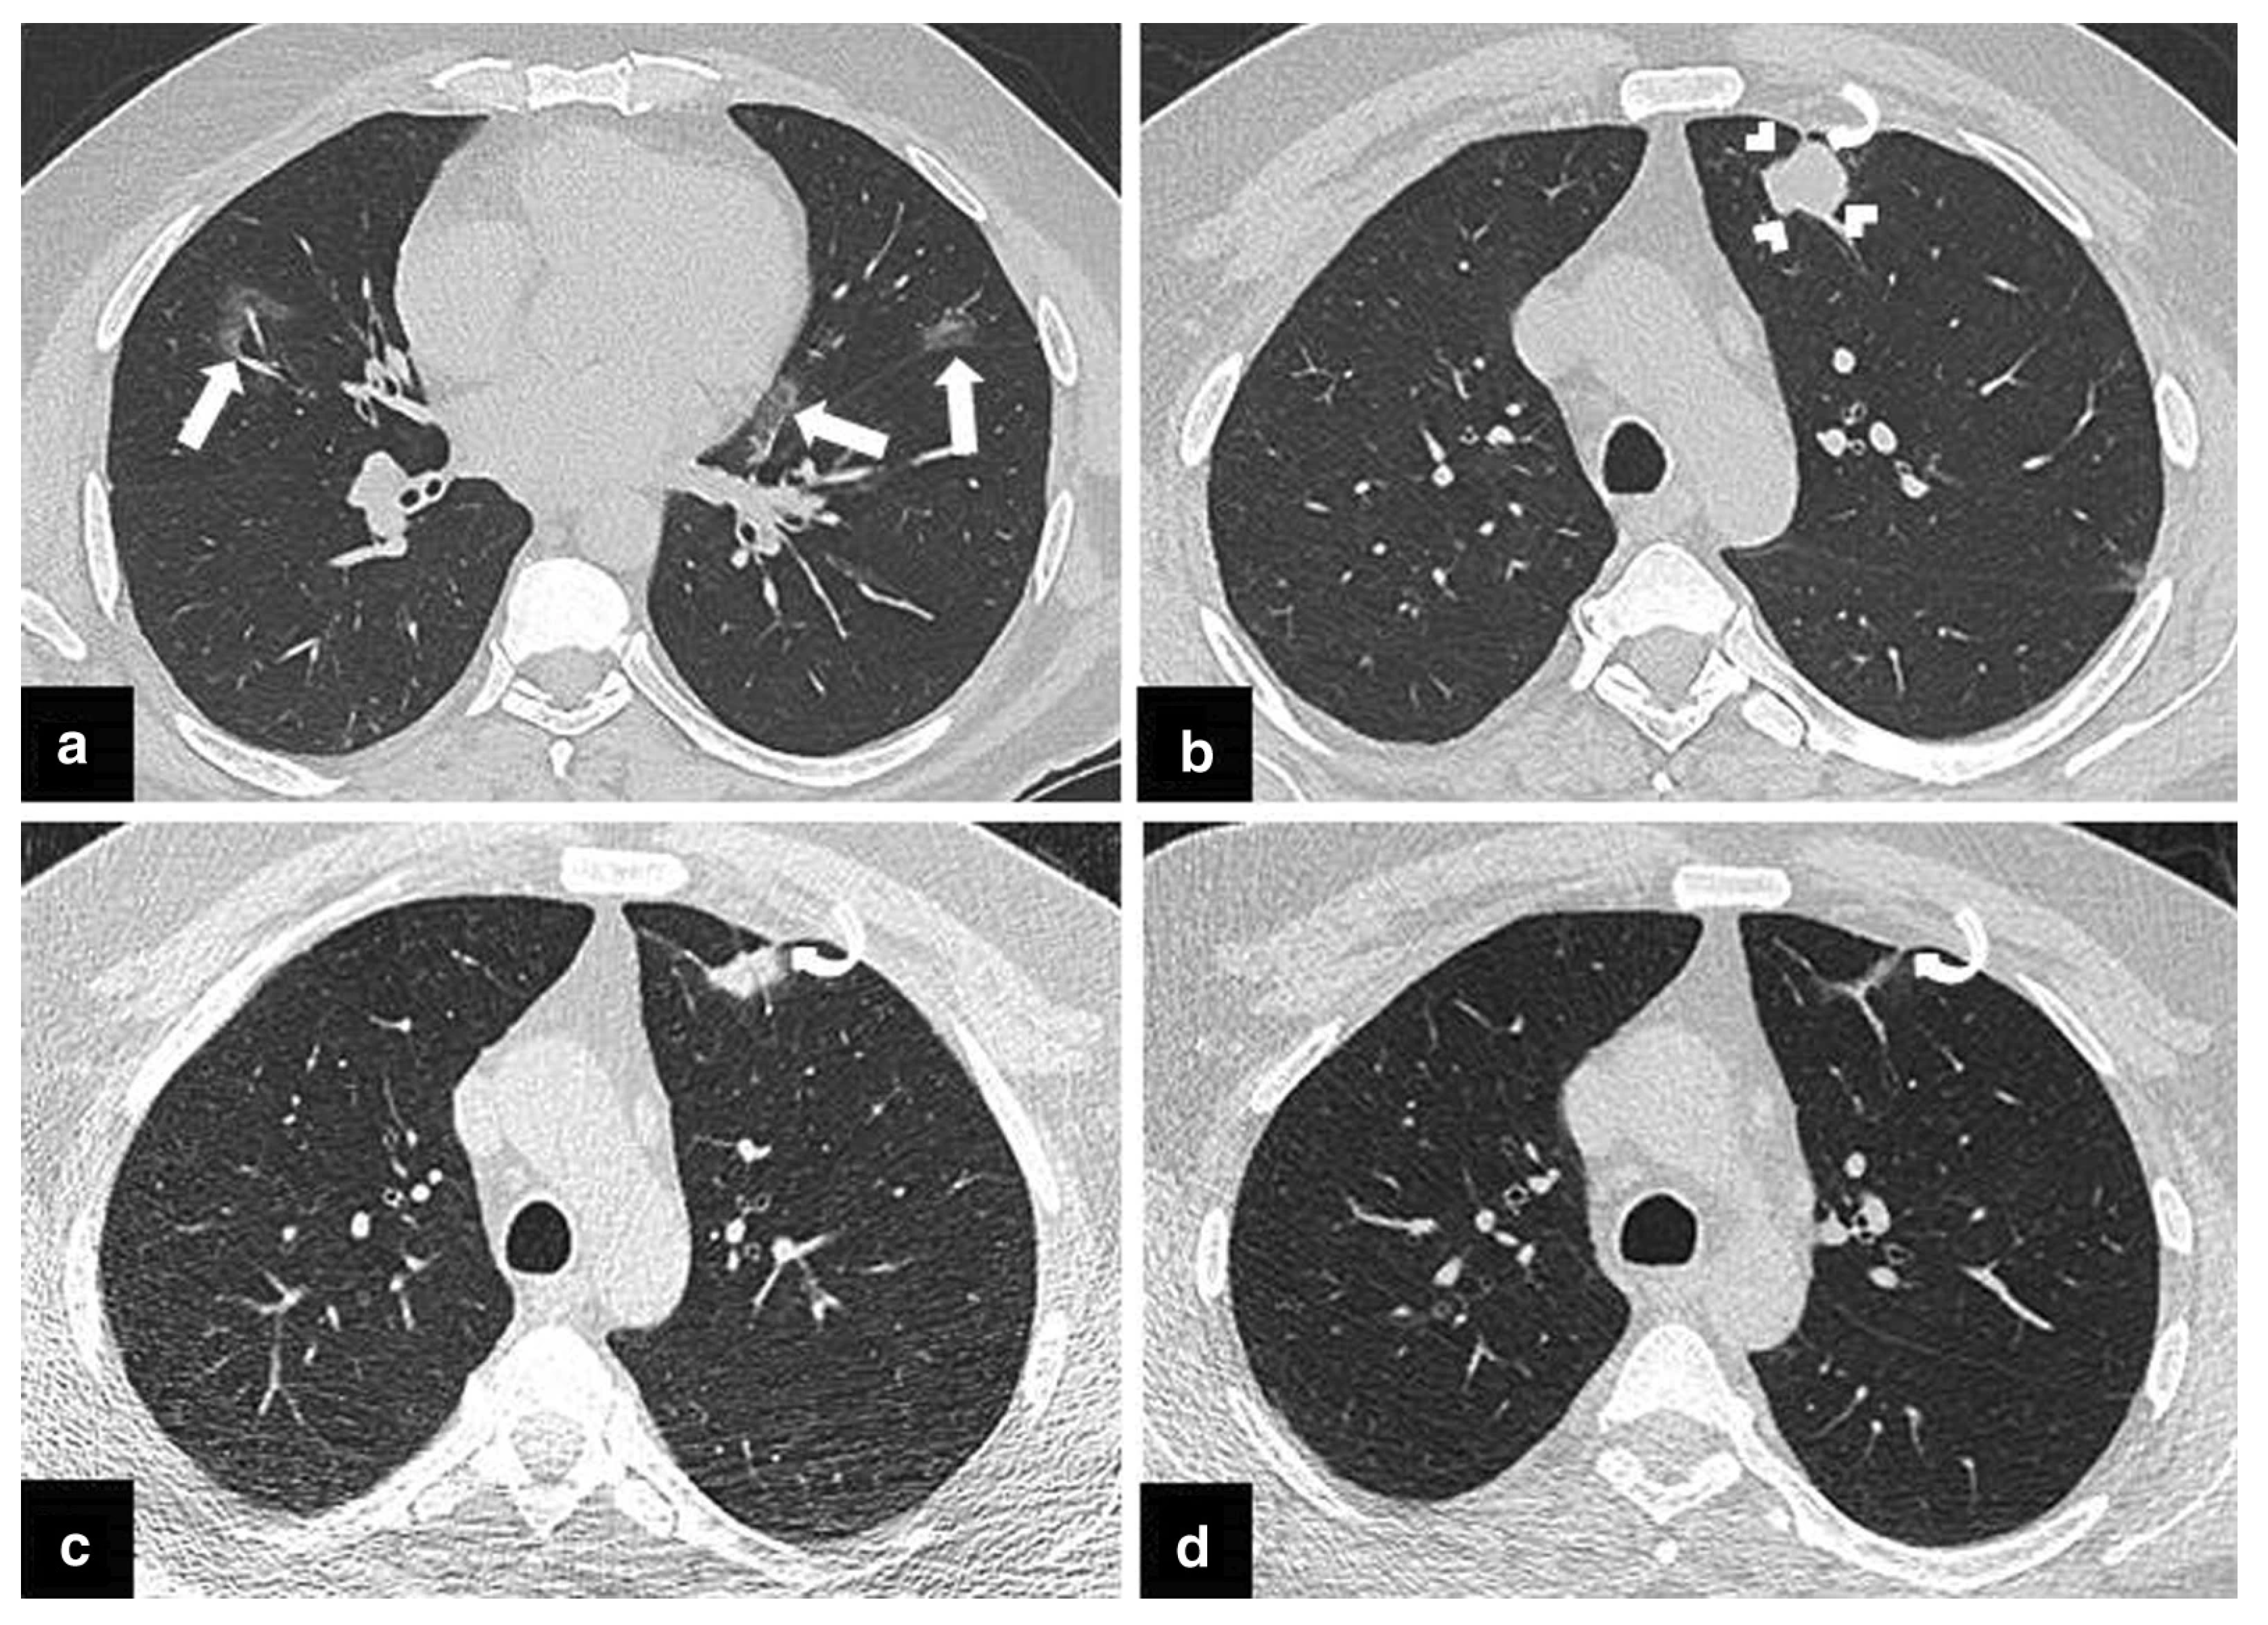

- Cognitive Bias

- Ciello, A.; Franchi, P.; Contegiacomo, A.; Cicchetti, G.; Bonomo, L.; Larici, A. Missed lung cancer: When, where, and why? Diagn. Interv. Radiol. 2017, 23, 118. [Google Scholar] [CrossRef] [PubMed] [Green Version]